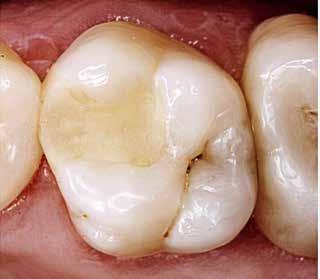

En dybtliggende amalgam-misfarvning udgør en af de mest vanskelige udfordringer ved udskiftning af restaureringer. Transcend Universal Body farven blev anvendt til at erstatte amalgamen, uden brug af blokeringsmateriale. Bemærk, hvor fremragende farven blender ind i den bevarede crista obliqua.

Før Efter